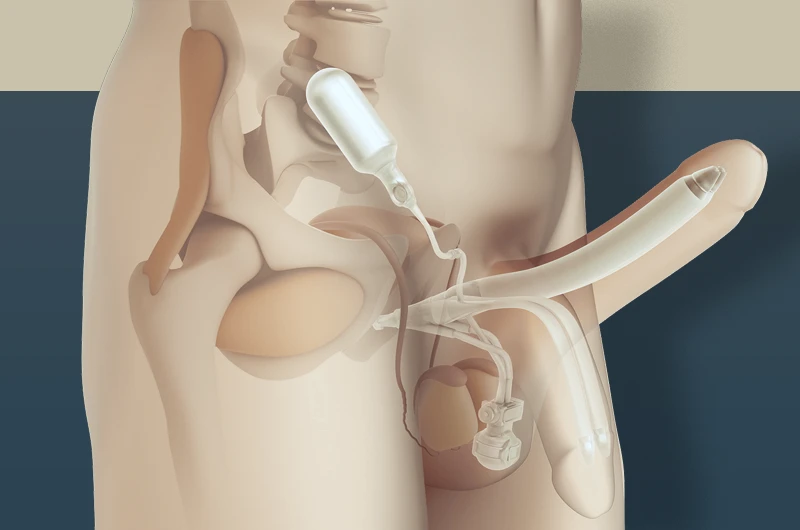

2. Melhora da libido e da saúde sexual

A testosterona é essencial para o desejo sexual masculino. Com a reposição, muitos pacientes relatam aumento da libido, melhor desempenho e mais satisfação nas relações.